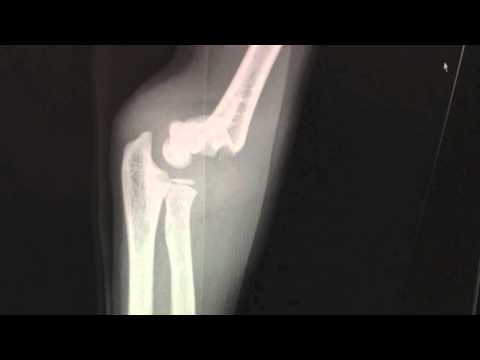

XR | Supracondylar Fractures